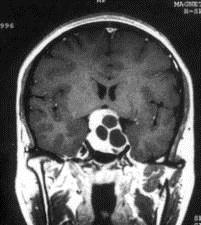

问题 病历摘要:??患者男性,35岁。性功能减退2年,视力下降6月。既往体健。体检:神清,皮肤细腻,毛发稀疏。视力左眼0.3,右眼0.5,双瞳等大等圆,直径3.5mm,对光反射稍迟钝,双颞侧偏盲,双眼底视神经乳头原发性萎缩,余神经系统未见异常。 垂体腺瘤目前主要治疗方法有哪些?

选项 A.溴隐亭、生长抑素等药物治疗 B.化疗 C.立体定向放射治疗 D.经蝶窦入路肿瘤切除 E.翼点开颅肿瘤切除 F.经额叶入路肿瘤切除 G.Krause入路肿瘤切除

答案 ACDEF